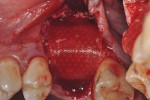

Each socket was treated in one of two manners. If the walls of the socket were determined to be thick and intact, with the diameter not larger than 7 mm to 8 mm, a barrier alone was trimmed to extend 3 mm beyond the socket and placed over the site. If the walls were thinner or if dehiscence or fenestrations were present at the socket, then a bone replacement graft of freeze-dried bone allograft (FDBA) (OraGraft®, LifeNet Health, Inc., www.accesslifenethealth.org) that was hydrated with either sterile water or recombinant platelet-derived growth factor-BB (rh-PDGF-BB) (Osteohealth, www.osteohealth.com) (Figure 2) was placed into the socket and was condensed with light incremental pressure to fill the socket. In two instances a bovine-derived xenograft (BioOss®, Osteohealth) was used mixed with rh-PDGF-BB, as a concurrent internal sinus lift was performed. The polylactic barrier was trimmed to fit the site (Figure 3) so that it also covered the areas where dehiscence or fenestrations were present in the buccal or lingual plate. Flaps were replaced back over the edges of the membrane without purposefully advancing them to achieve primary coverage. The site was sutured with 6-0 expanded polytetrafluoroethylene (ePTFE) (Gore-Tex®, W.L. Gore & Associates, www.gore.com) (Figure 4). For infection control, patients were prescribed amoxicillin 875 mg to be taken twice daily for 7 days, along with topically applying chlorhexidine 0.12% mouthrinse with a cotton swab to the site twice daily for 1 month. If a patient was allergic to amoxicillin, they were prescribed either clindamycin 150 mg four times daily for 7 days, or azithromycin 250 mg with two pills taken on the first day and then one per day for an additional 4 days. Ibuprofen 600 mg or acetominophen with codeine were used for analgesia. Patients were told to refrain from chewing on the site to avoid dislodging the barrier.